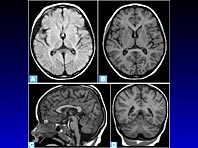

Новое исследование обнаружило связь между здоровьем мозга и лептином — гормоном насыщения. Если вы постоянно чувствуете голод, это может быть нехорошим симптомом. В последние годы появляется все больше доказательств того, что ожирение в среднем возрасте — это серьезный риск развития деменции. Изучение жировой ткани показало, что это не просто резервуар для хранения энергии, а часть…